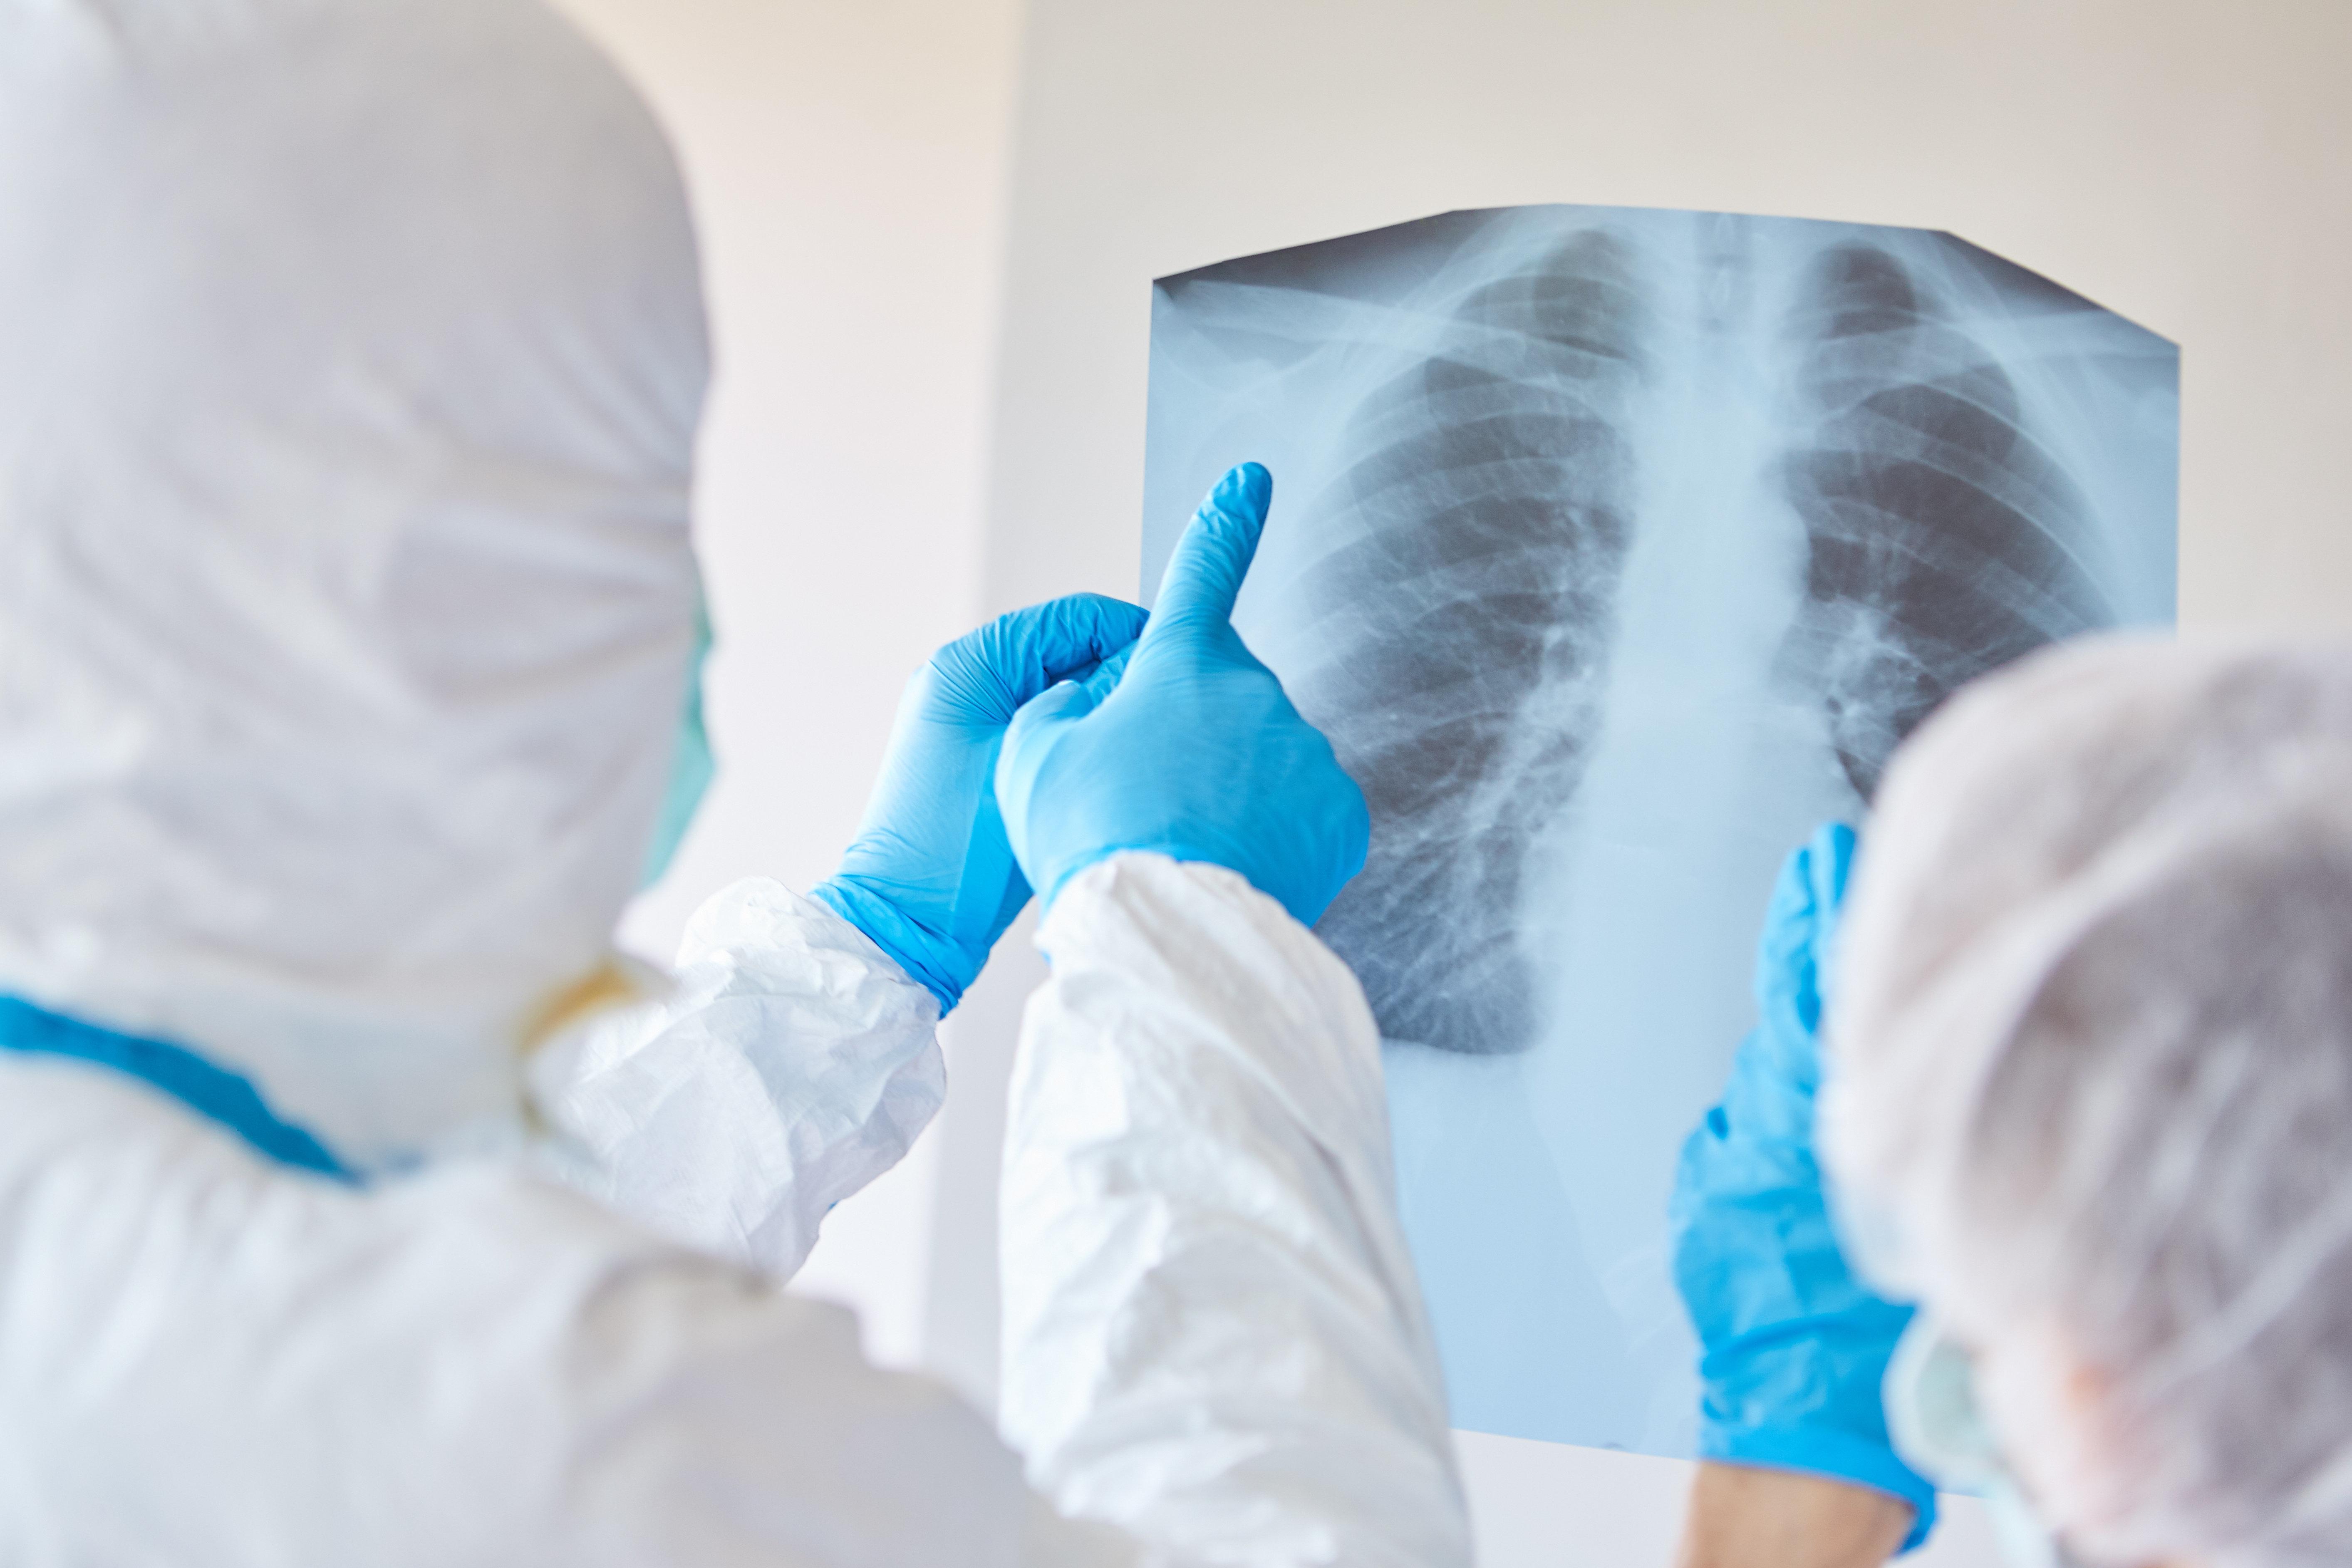

Was Covid 19 In Der Lunge Anrichtet

Simulation Zeigt Ausmass Was Covid 19 In Der Lunge Anrichtet Mz De

Virenschaden Und Entzundungen Das Macht Covid 19 Mit Der Lunge Bildderfrau De

Coronavirus Video Zeigt Was Covid 19 In Der Lunge Anrichtet

Was Das Coronavirus In Der Lunge Anrichtet Wissenschaft De

Welche Sichtbaren Schaden Covid 19 In Der Lunge Anrichtet Video